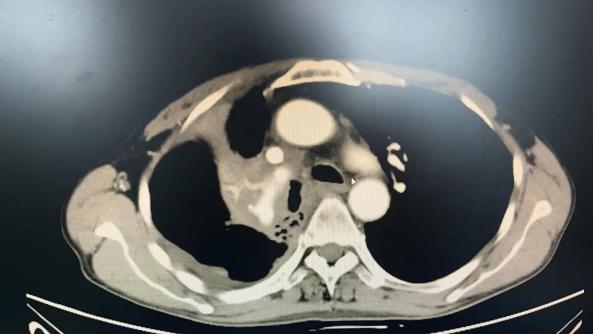

载药微球化疗栓塞(DEB-BACE)治疗晚期肺癌患者1例

2023-05-29 16:20